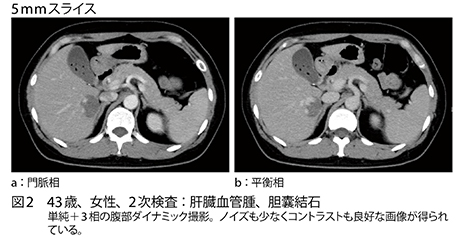

■Aquilion Lightning / Helios Editionによる臨床画像

Aquilion Lightning / Helios Edition では、肺がんCT検診はもちろん胸部CTの精査目的での撮影で、短時間で低線量かつ高画質の検査が可能になった。森部長は、「撮影時間は4列CTの約20秒から約4秒と大きく短縮し、息止め時間が短くなり受診者の負担軽減になっています。また、最新鋭CTの導入は、スタッフのモチベーションアップにもつながっています」と評価する。同クリニックでは、放射線診断医1名が常勤し画像診断を行っているが、新しいCTでは画質が向上し情報量が増えたと評価しているという。画像の提供は、4列CT時の10mmから5mm再構成に変更した。現在はaxial画像で提供しているが、今後sagittalやcoronal画像の作成やMPRでの提供などを検討していきたいと森部長は述べる。